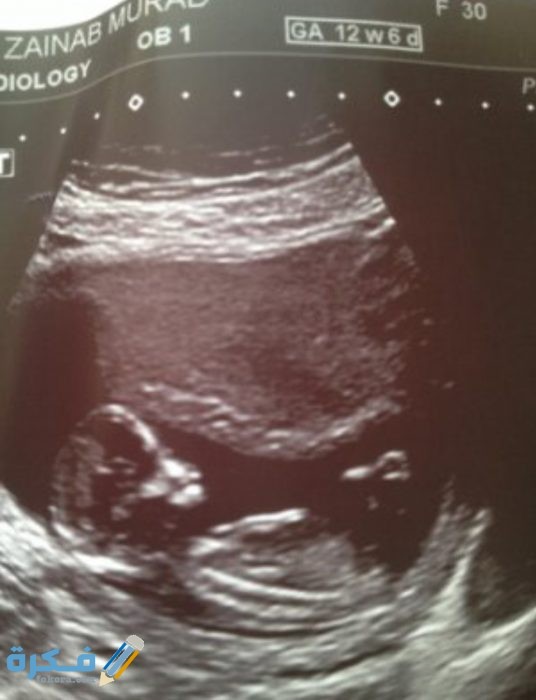

شكل الجنين في السونار :

يختلف السونار الخاص بالولد والبنت والاختلافات هي :

- يتم معرفة نوع الجنين في الشهر الرابع من الحمل لأن الذي يميز الذكر في السونار وجود شئ يشبه السلحفاة بين قدمي الجنين وهو العضو الذكري وكلما كان واضحا ومنتصبا أكد ذلك علي نوعية الجنين بشكل دقيق .

- عندما يكون الجنين انثى يجد الأطباء صعوبة في تحديد النوع وذلك لعدم وضوح العضو التناسلي الخاص بالأنثى والذي غالبا ما يشبه شطيرة الهمبرجر حيث أن لأن الشفرتين يشبهان طبقتي الخبز والبظر يشبه شريحة اللحم الموجودة وسط الشطيرة .